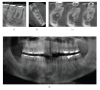

Cone Beam Computed Tomography (CBCT) is a diagnostic imaging modality that provides high-quality, accurate three-dimensional (3D) representations of the osseous elements of the maxillofacial skeleton. CBCT systems are available that provide small field of view images at low dose with sufficient spatial resolution for applications in endodontic diagnosis, treatment guidance, and posttreatment evaluation. This article provides a literature review and pictorial demonstration of CBCT as an imaging adjunct for endodontics.